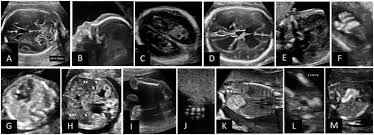

Here are common soft markers that show up in the second-trimester ultrasound. Mid-trimester soft markers have been linked with Down syndrome and other aneuploidies. Thickened nuchal fold echogenic bowel shortened femur shortened humerus pyelectasis and absent or hypoplastic nasal bone.

Ultrasound is a key component of aneuploidy screening. Ultrasonically echoreflective bowel bright gut short femurs clinodactyly of the fifth digit and oddly shaped heads have all been identified as soft markers associated with an increased risk of trisomy. Soft markersDown syndrome.

Down Syndrome can include cardiovascular central. A review on the various soft markers identified for the detection of down syndrome from the first and second trimester ultrasound fetal images has been made. In this low risk population soft markers were found in 59 of fetuses at second trimester ultrasound.

There are specific characteristics identified during an ultrasound exam in the second trimester of a womans pregnancy that are possible indicators for Downs syndrome. Both major structural abnormalities and minor soft markers can be detected by ultrasound in fetuses affected with aneuploidies. There are many other prenatal screening tests available with better detection rates for Down syndrome than the mid-trimester ultrasound.

Markers were isolated in 51 multiple in 07 and combined with anomalies in 01 1. Most of the time this represents nothing but in some cases it may be caused by Down syndrome cytomegalovirus CMV. The following are ultrasound markers that are seen more frequently in fetuses with Down syndrome. The 1st 2nd trimesters can show anatomical signs frequently seen in fetuses with Down Syndrome or other genetic accidents that result in 3 copies of a specific chromosomeKnowing your risk of DS calculated by FUS findings gestational maternal age 1st 2nd trimester maternal blood screens a higher-resolution FUS helps you decide if you want. Most cases 95 had a single marker 4 had two markers and 1 had three or more markers when soft markers were first identified 10. They do not affect the function of the muscle or the beating of the heart. But there is nothing to worry about and my child is perfectly normal Becauese my first-trimester scan and blood test were both normalBUT I need to make an appointment with a genetic. Markers were isolated in 51 multiple in 07 and combined with anomalies in 01 1. And a day after my midwife called me and told me that they found two soft markers for down syndrome.

Also what are the signs of Down syndrome in an ultrasound. This is a relatively common finding on ultrasound. They do not affect the function of the muscle or the beating of the heart. Certain features detected during a second trimester ultrasound exam are potential markers for Downs syndrome and they include dilated brain ventricles absent or small nose bone increased. Most cases 95 had a single marker 4 had two markers and 1 had three or more markers when soft markers were first identified 10. The 1st 2nd trimesters can show anatomical signs frequently seen in fetuses with Down Syndrome or other genetic accidents that result in 3 copies of a specific chromosomeKnowing your risk of DS calculated by FUS findings gestational maternal age 1st 2nd trimester maternal blood screens a higher-resolution FUS helps you decide if you want. But there is nothing to worry about and my child is perfectly normal Becauese my first-trimester scan and blood test were both normalBUT I need to make an appointment with a genetic.